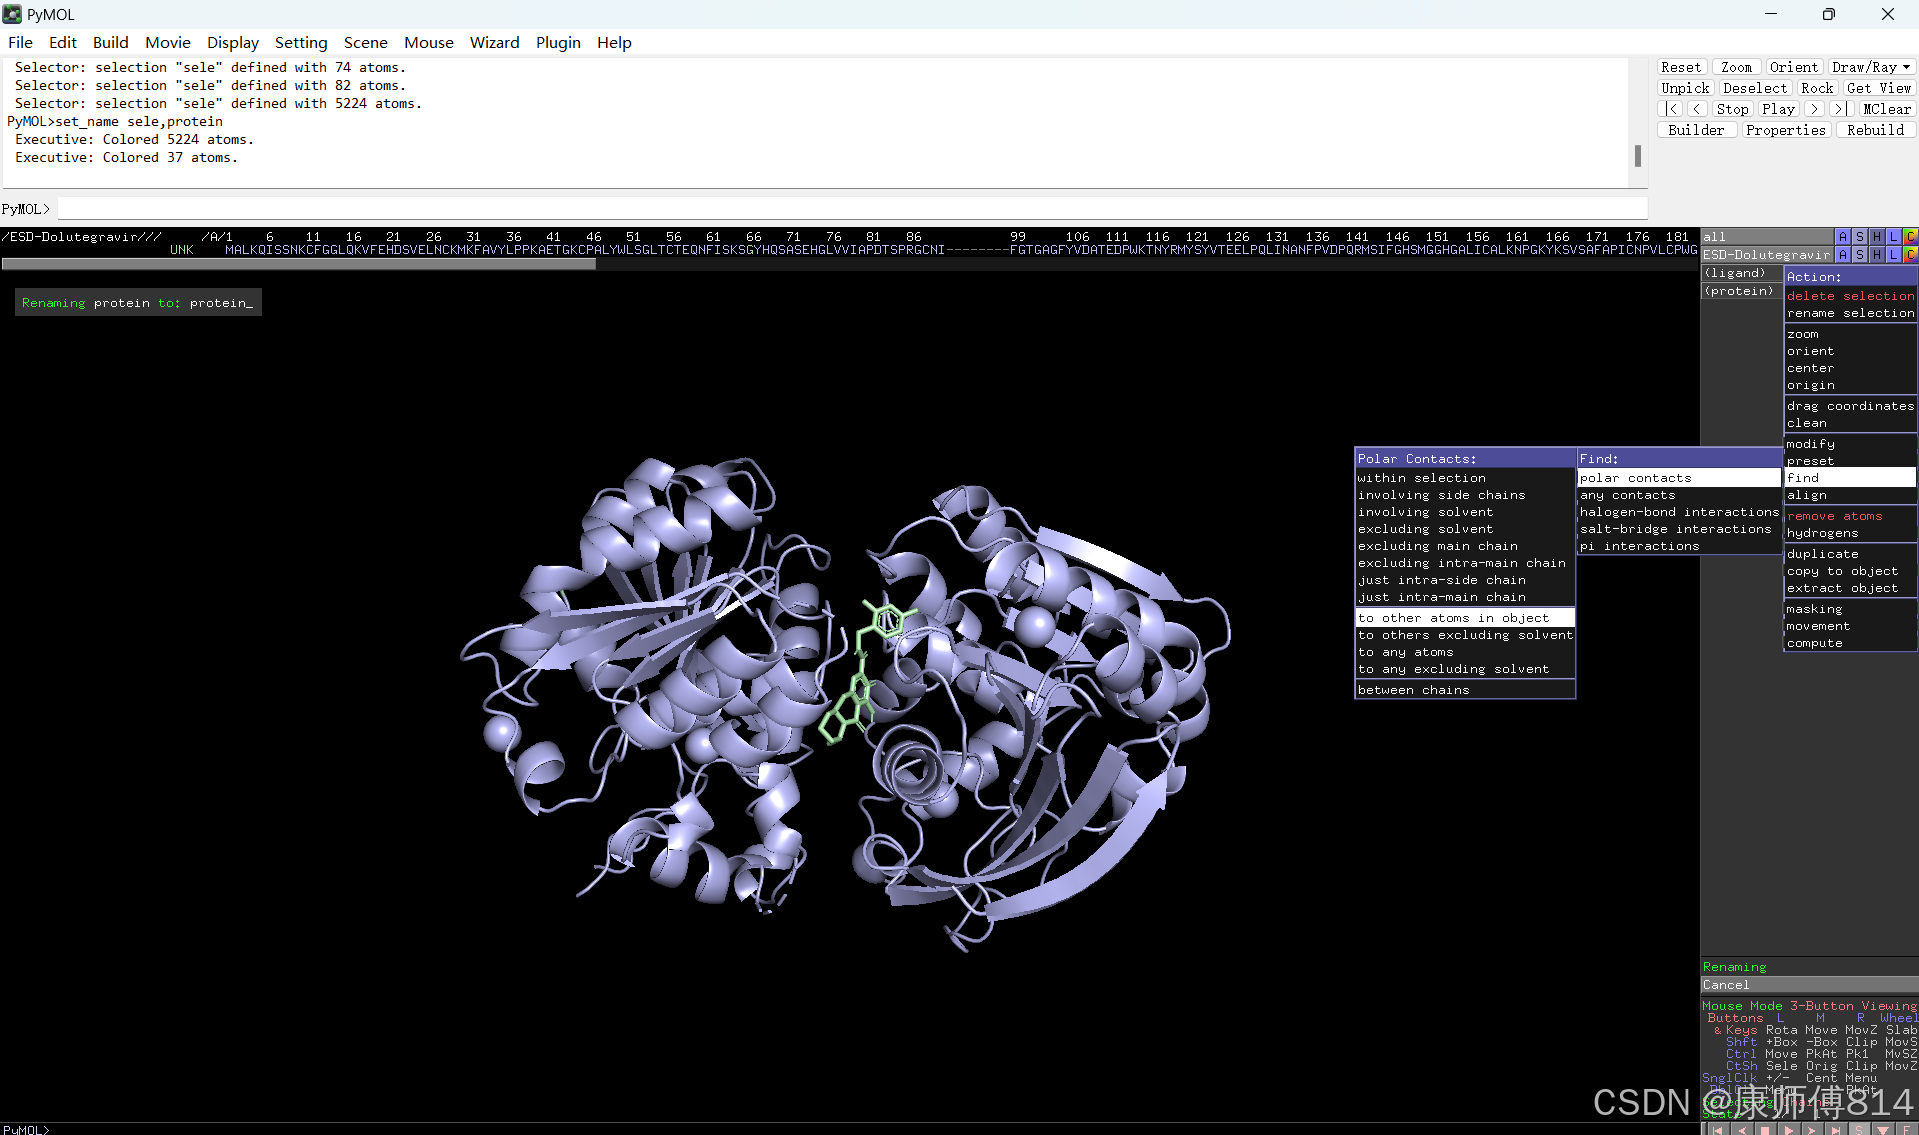

#选中小分子,按以下顺序点击以显示结合位点的氢键

#选中蛋白,点击show-sticks显示氨基酸棍状结构,右下角Selecting修改为Residues模式,选中与小分子连接的氨基酸残基,命名为A,并更改颜色

#点击蛋白,点击H-sicks隐藏蛋白棍状结构,然后显示小分子结合位点氨基酸残基棍状结构